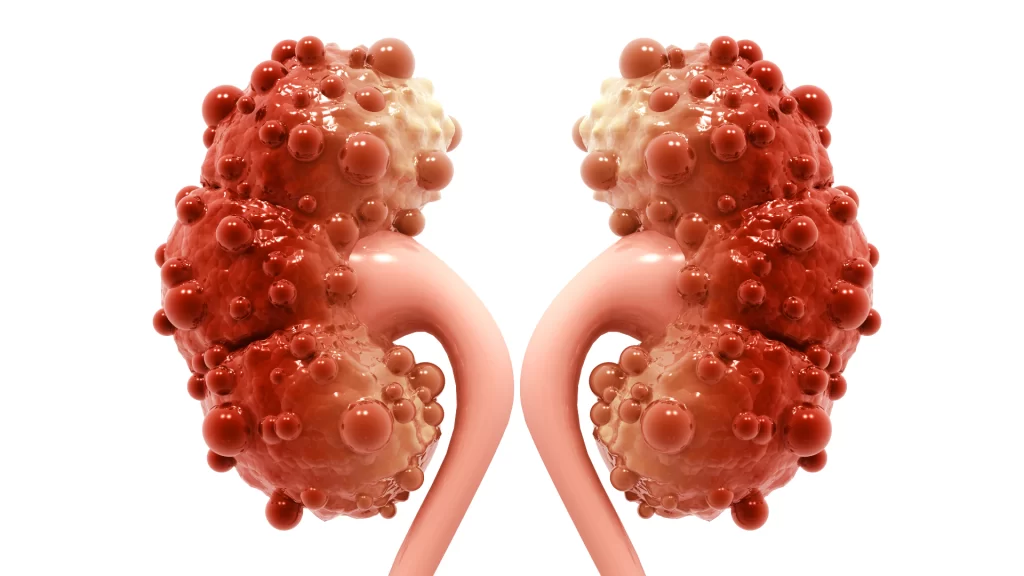

Polycystic Kidney Disease (PKD) Management

Polycystic Kidney Disease (PKD) management focuses on alleviating symptoms and preventing complications. Lifestyle modifications, including a low-sodium diet and regular exercise, contribute to overall kidney health. Medications may be prescribed to control blood pressure and manage associated symptoms. Close monitoring of kidney function through regular check-ups is crucial. In advanced cases, where cysts lead to severe complications, interventions such as cyst aspiration or surgery may be considered.